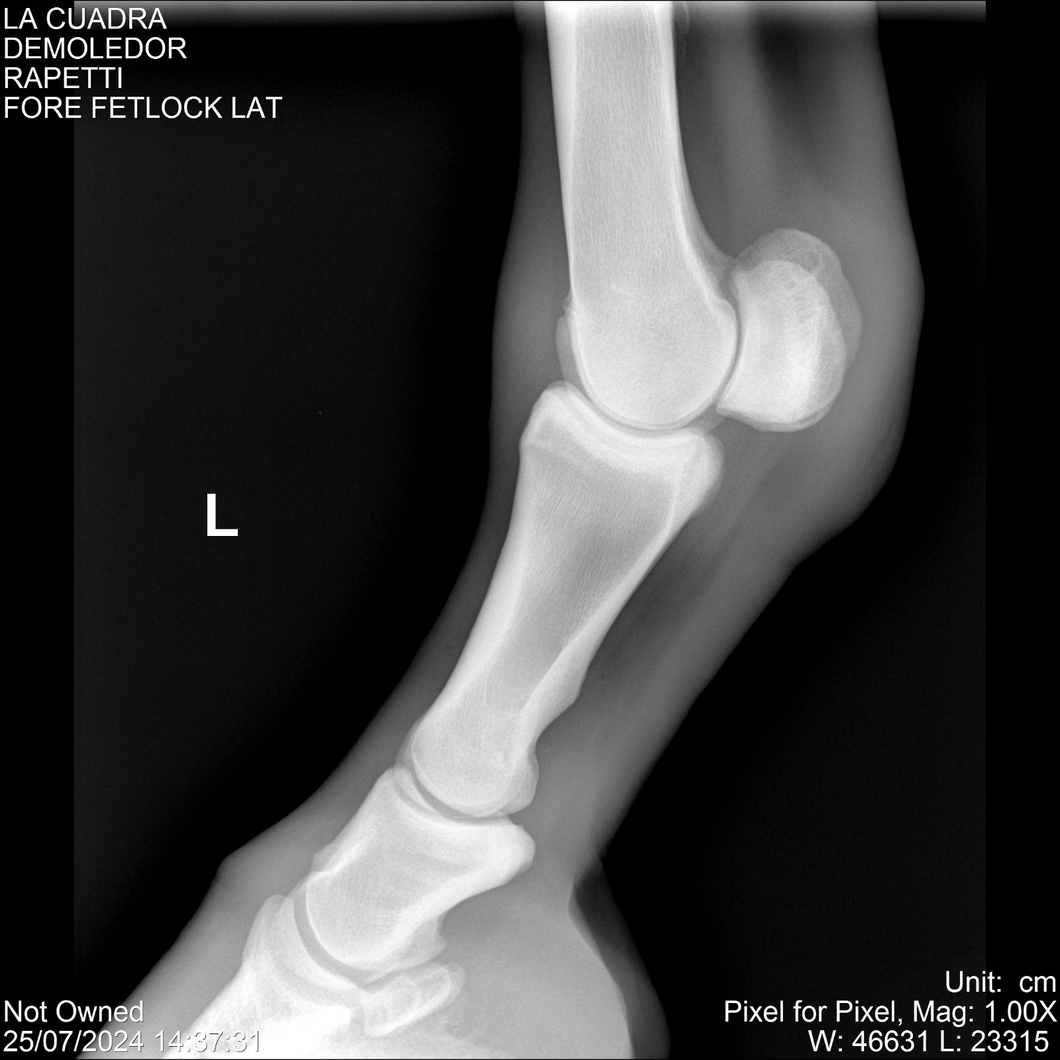

LOTE 14, DEMOLEDOR 🔥 🔥 🔥 Lote Anterior Volver al remate Lote Siguiente Ficha Contacto Montevideo - Ficha del Lote Identificador: #284454 Categoría: Yeguarizos Montevideo - 89 Visualizaciones ClicData Contacto Empresa: Abelenda N. R., Walter Hugo Nombre*: Teléfono* : E-mail* : Mensaje Enviar Registrese gratis Este contenido Exclusivo está disponible sólo para usuarios registrados Ingresar